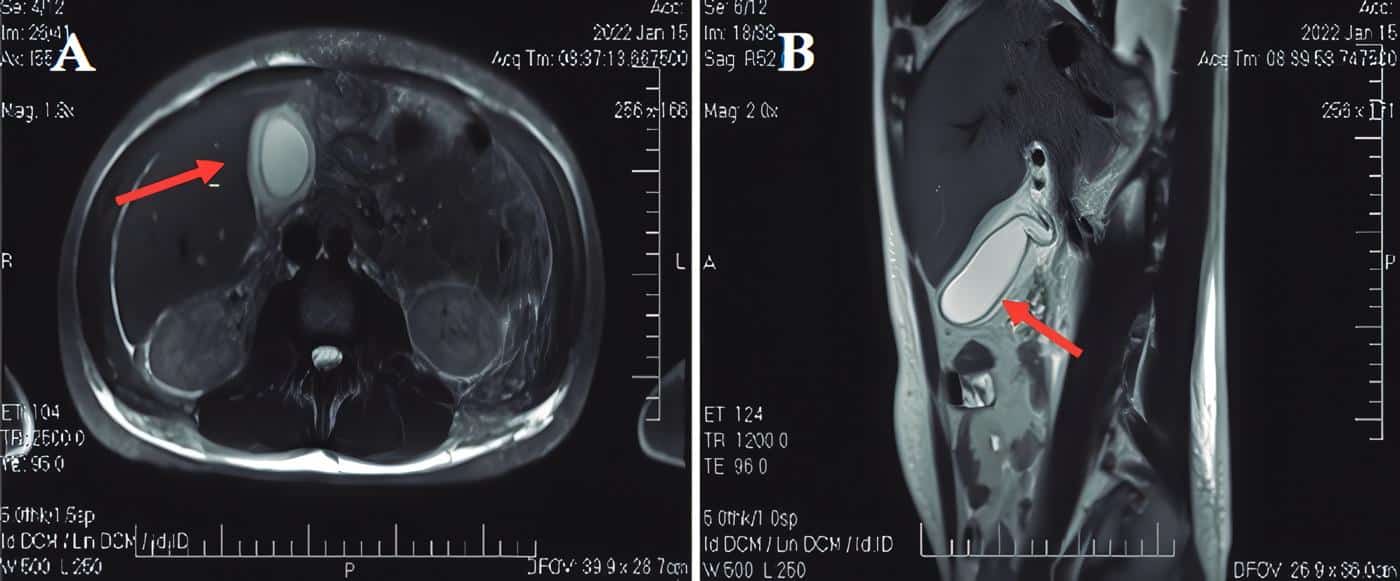

Upon physical examination, he presented normotensive, normal respiratory rate, adequate ambient oxygen saturation, afebrile, mild tachycardia without cardiopulmonary alterations, and soft abdomen with sensation of a painful mass in the right hypochondrium, but without signs of peritoneal irritation. Paraclinical tests showed leukocytosis, direct hyperbilirubinemia, and an alanine aminotransferase-alkaline phosphatase (ALT/ AP) ratio of 0,56 suggestive of cholestasis, but otherwise normal liver profile. The abdominal ultrasound showed a partially distended gallbladder, with thickened walls (9.2 mm), but without endoluminal defects. General Surgery suspected AC with intermediate risk for choledocholithiasis and requested a Magnetic Resonance Cholangiography that showed a distended, stoneless gallbladder with thickened walls (7 mm) and a diagnosis of AC and hepatomegaly (Figure 1).

Figure 1. Magnetic Resonance Cholangiography. A. Axial view in T2. B. Sagittal view in T2. The arrows show the gallbladder with thickened walls, perivesicular fl uid, and no evidence of stones inside.